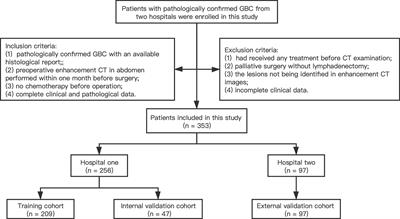

ORIGINAL RESEARCH

Published on 22 Sep 2021